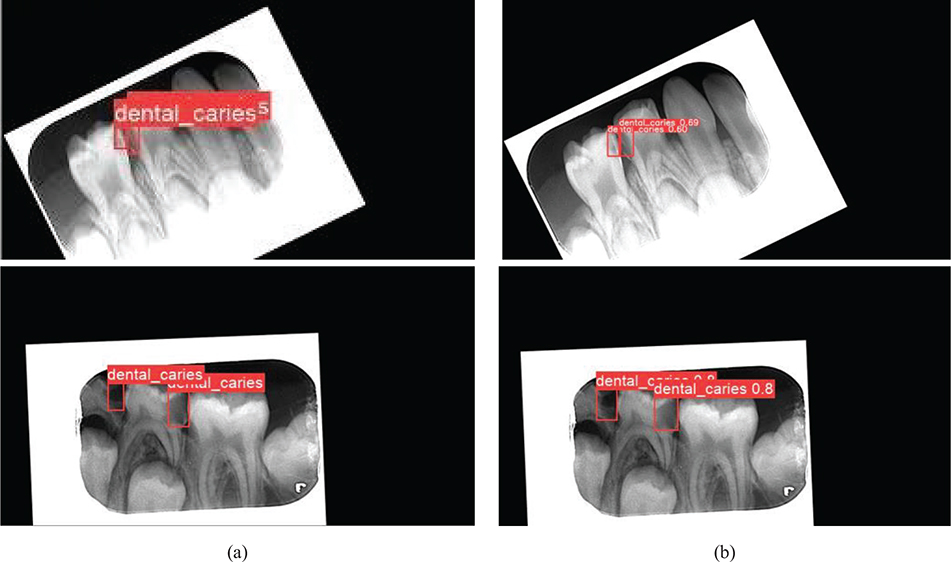

The data obtained from the various radiographic images in the dataset were augmented using the Python programming language and the Keras library. Data augmentation process: the images were realized by rotating the x‑y axes and changing the color tones. With the implementation of the data augmentation process, a total of 415 radiographic images were obtained. The augmented data are labeled in .txt format. In the labeling process, the approximal caries in the radiographic images are framed with a red box, and the coordinates of the caries are indicated. Two pediatric dentists served as observers during this process. The reliability of the observers was evaluated comparatively. After 10 days from the first observer’s assessment, the same observer performed re-labeling, and 96.6% consistency was observed between this labeling and the initial one. The second observer then labeled and 98.3% consistency was observed between the first observer. Figure 2 shows a few of the radiographic images labeled by pediatric dentists who specialize in pediatrics at the university.

Figure 2. Radiographic image samples labeled by a pediatric dentist.

The detection model was tested with the test dataset over the best weight values obtained as a result of 300 iterations of training. In Figure 5, the left-side images (Figure 5a) are the labeled test data, and the right-side images (Figure 5b) are the detection images predicted by the trained model.

Figure 5. Evaluation of the detection performance of the proposed AI-based model with a comparison between labeling and testing stages on the same radiographic images. (a) Radiographic images labeled by the pediatric dentist before training and testing process and (b) the output images from the test.